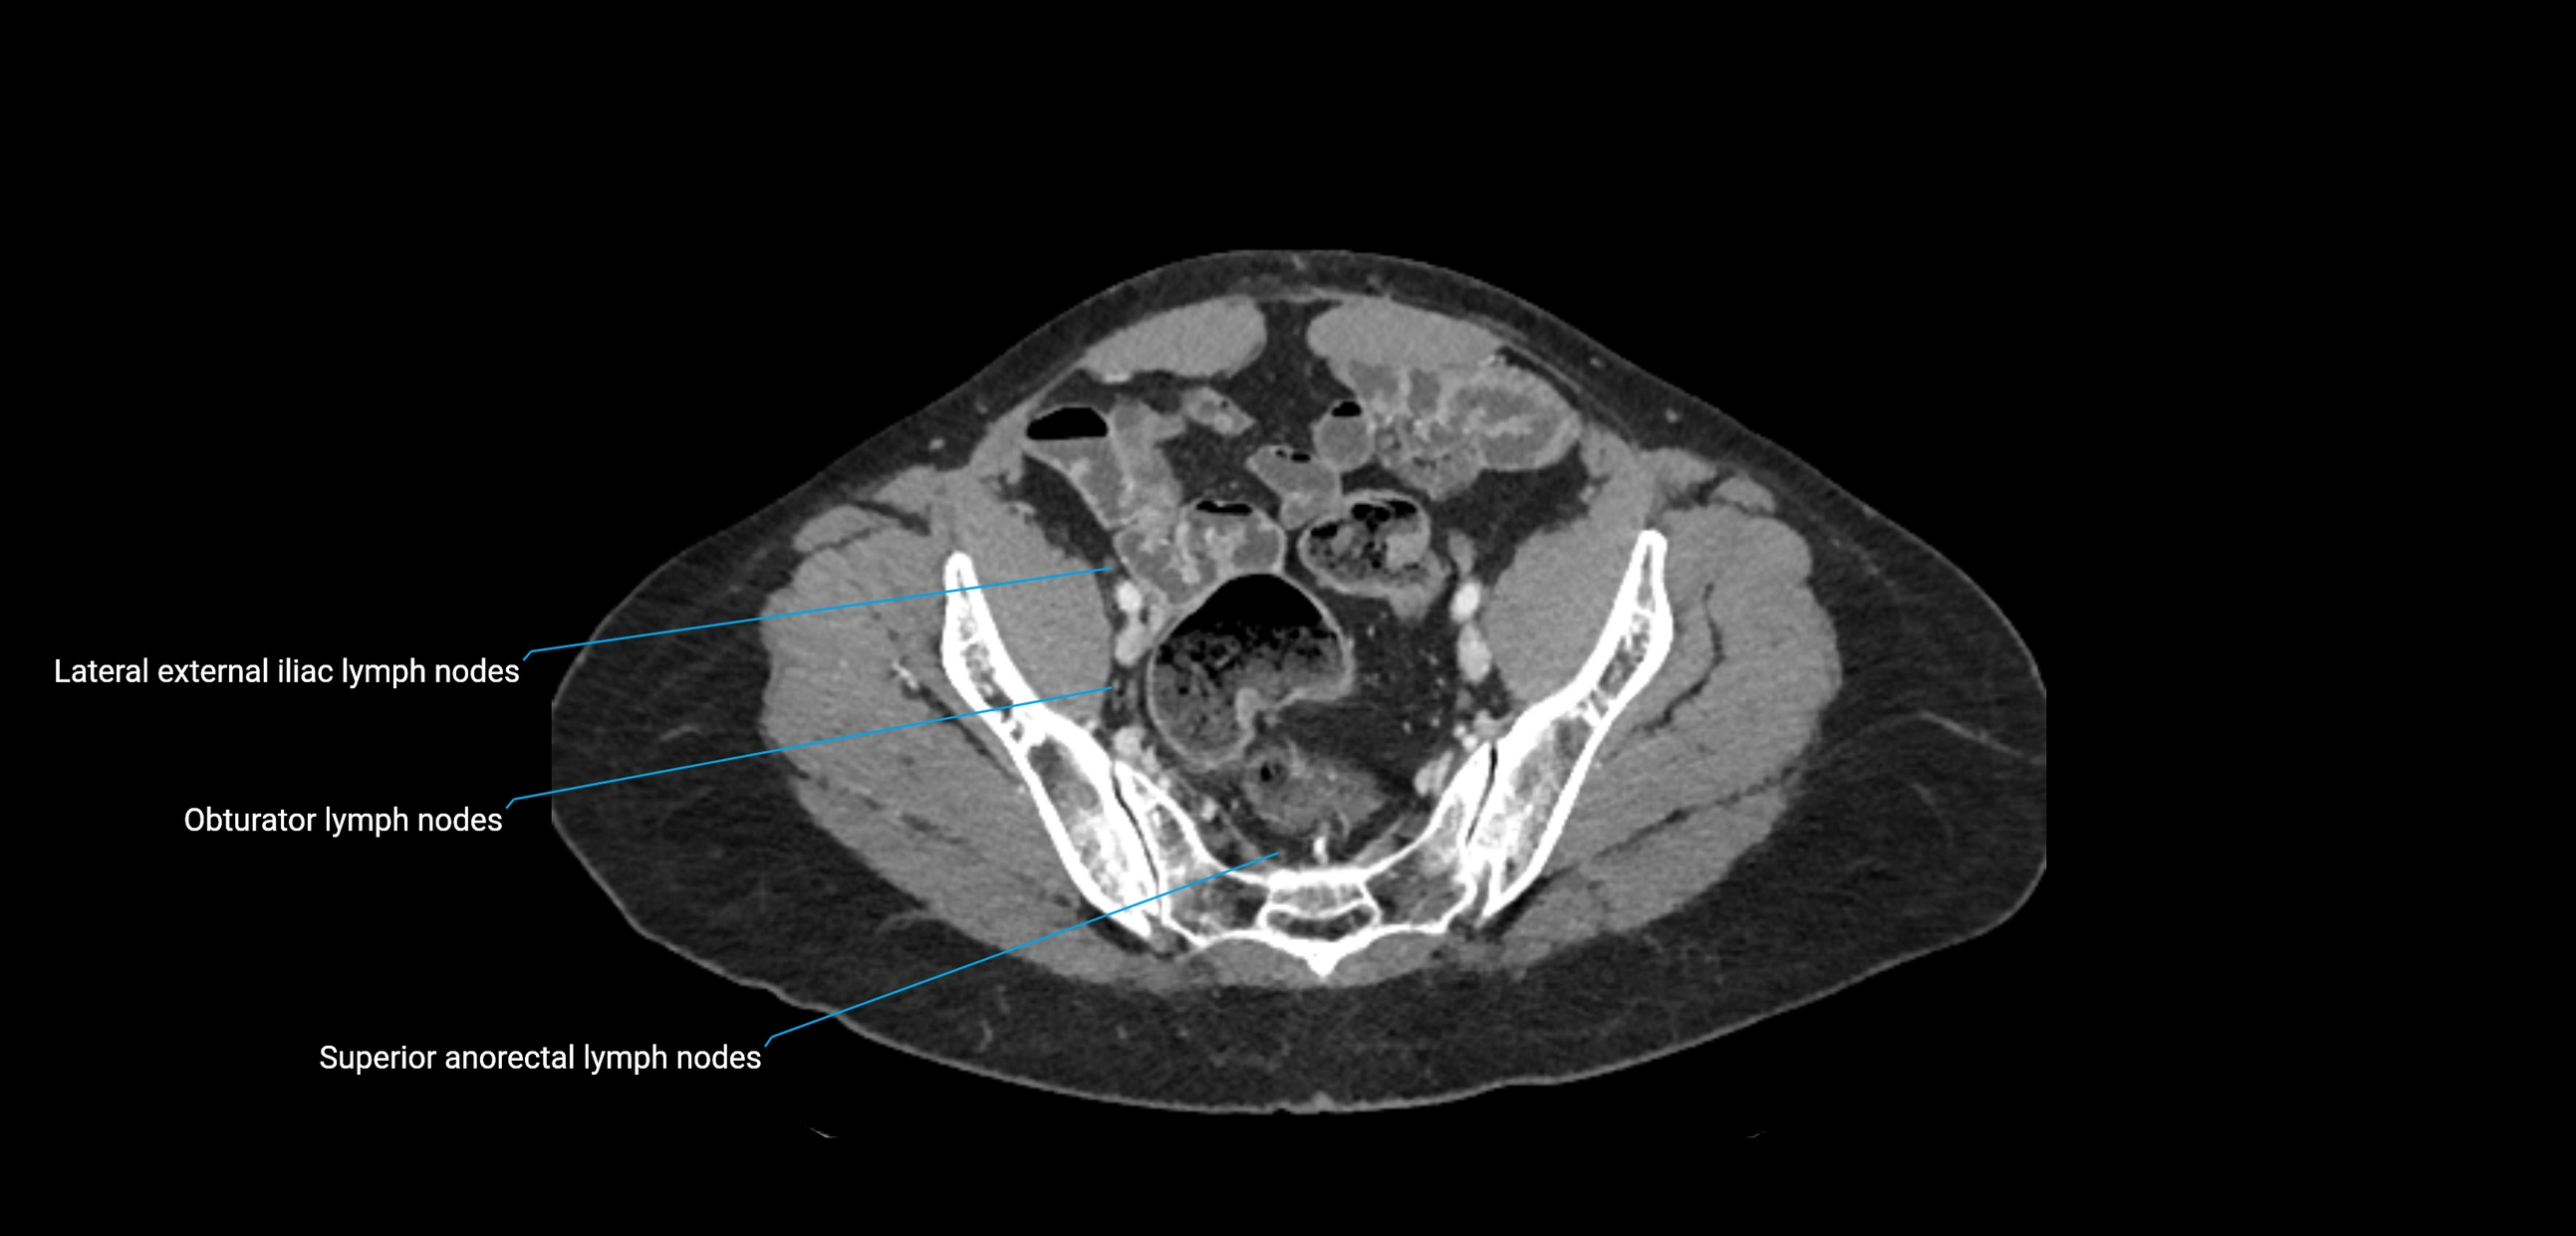

CT image

image